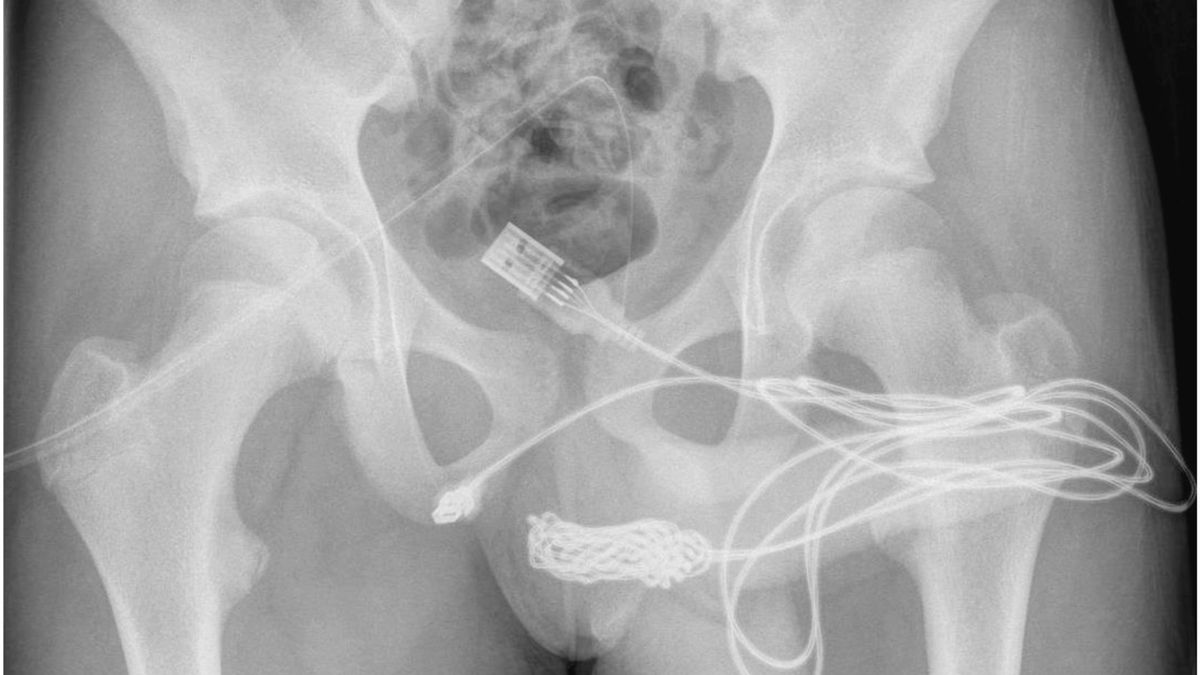

“Se descubrió que los dos puertos distales del cable USB sobresalían del meato uretral externo, mientras que la parte media del cable anudado permanecía dentro de la uretra“, detalló el informe médico registrado en noviembre de 2021, y que fue publicado recientemente por la revista científica Science Direct.

“Se realizó una incisión penoescrotal longitudinal, sobre el cuerpo extraño palpable, y se realizó una disección cuidadosa a través de los tejidos más profundos, dividiendo el músculo bulboesponjoso“, detallaron los especialistas.

Asimismo, indicaron que ambos extremos del cable USB “se sacaron con éxito a través del meato uretral externo”.